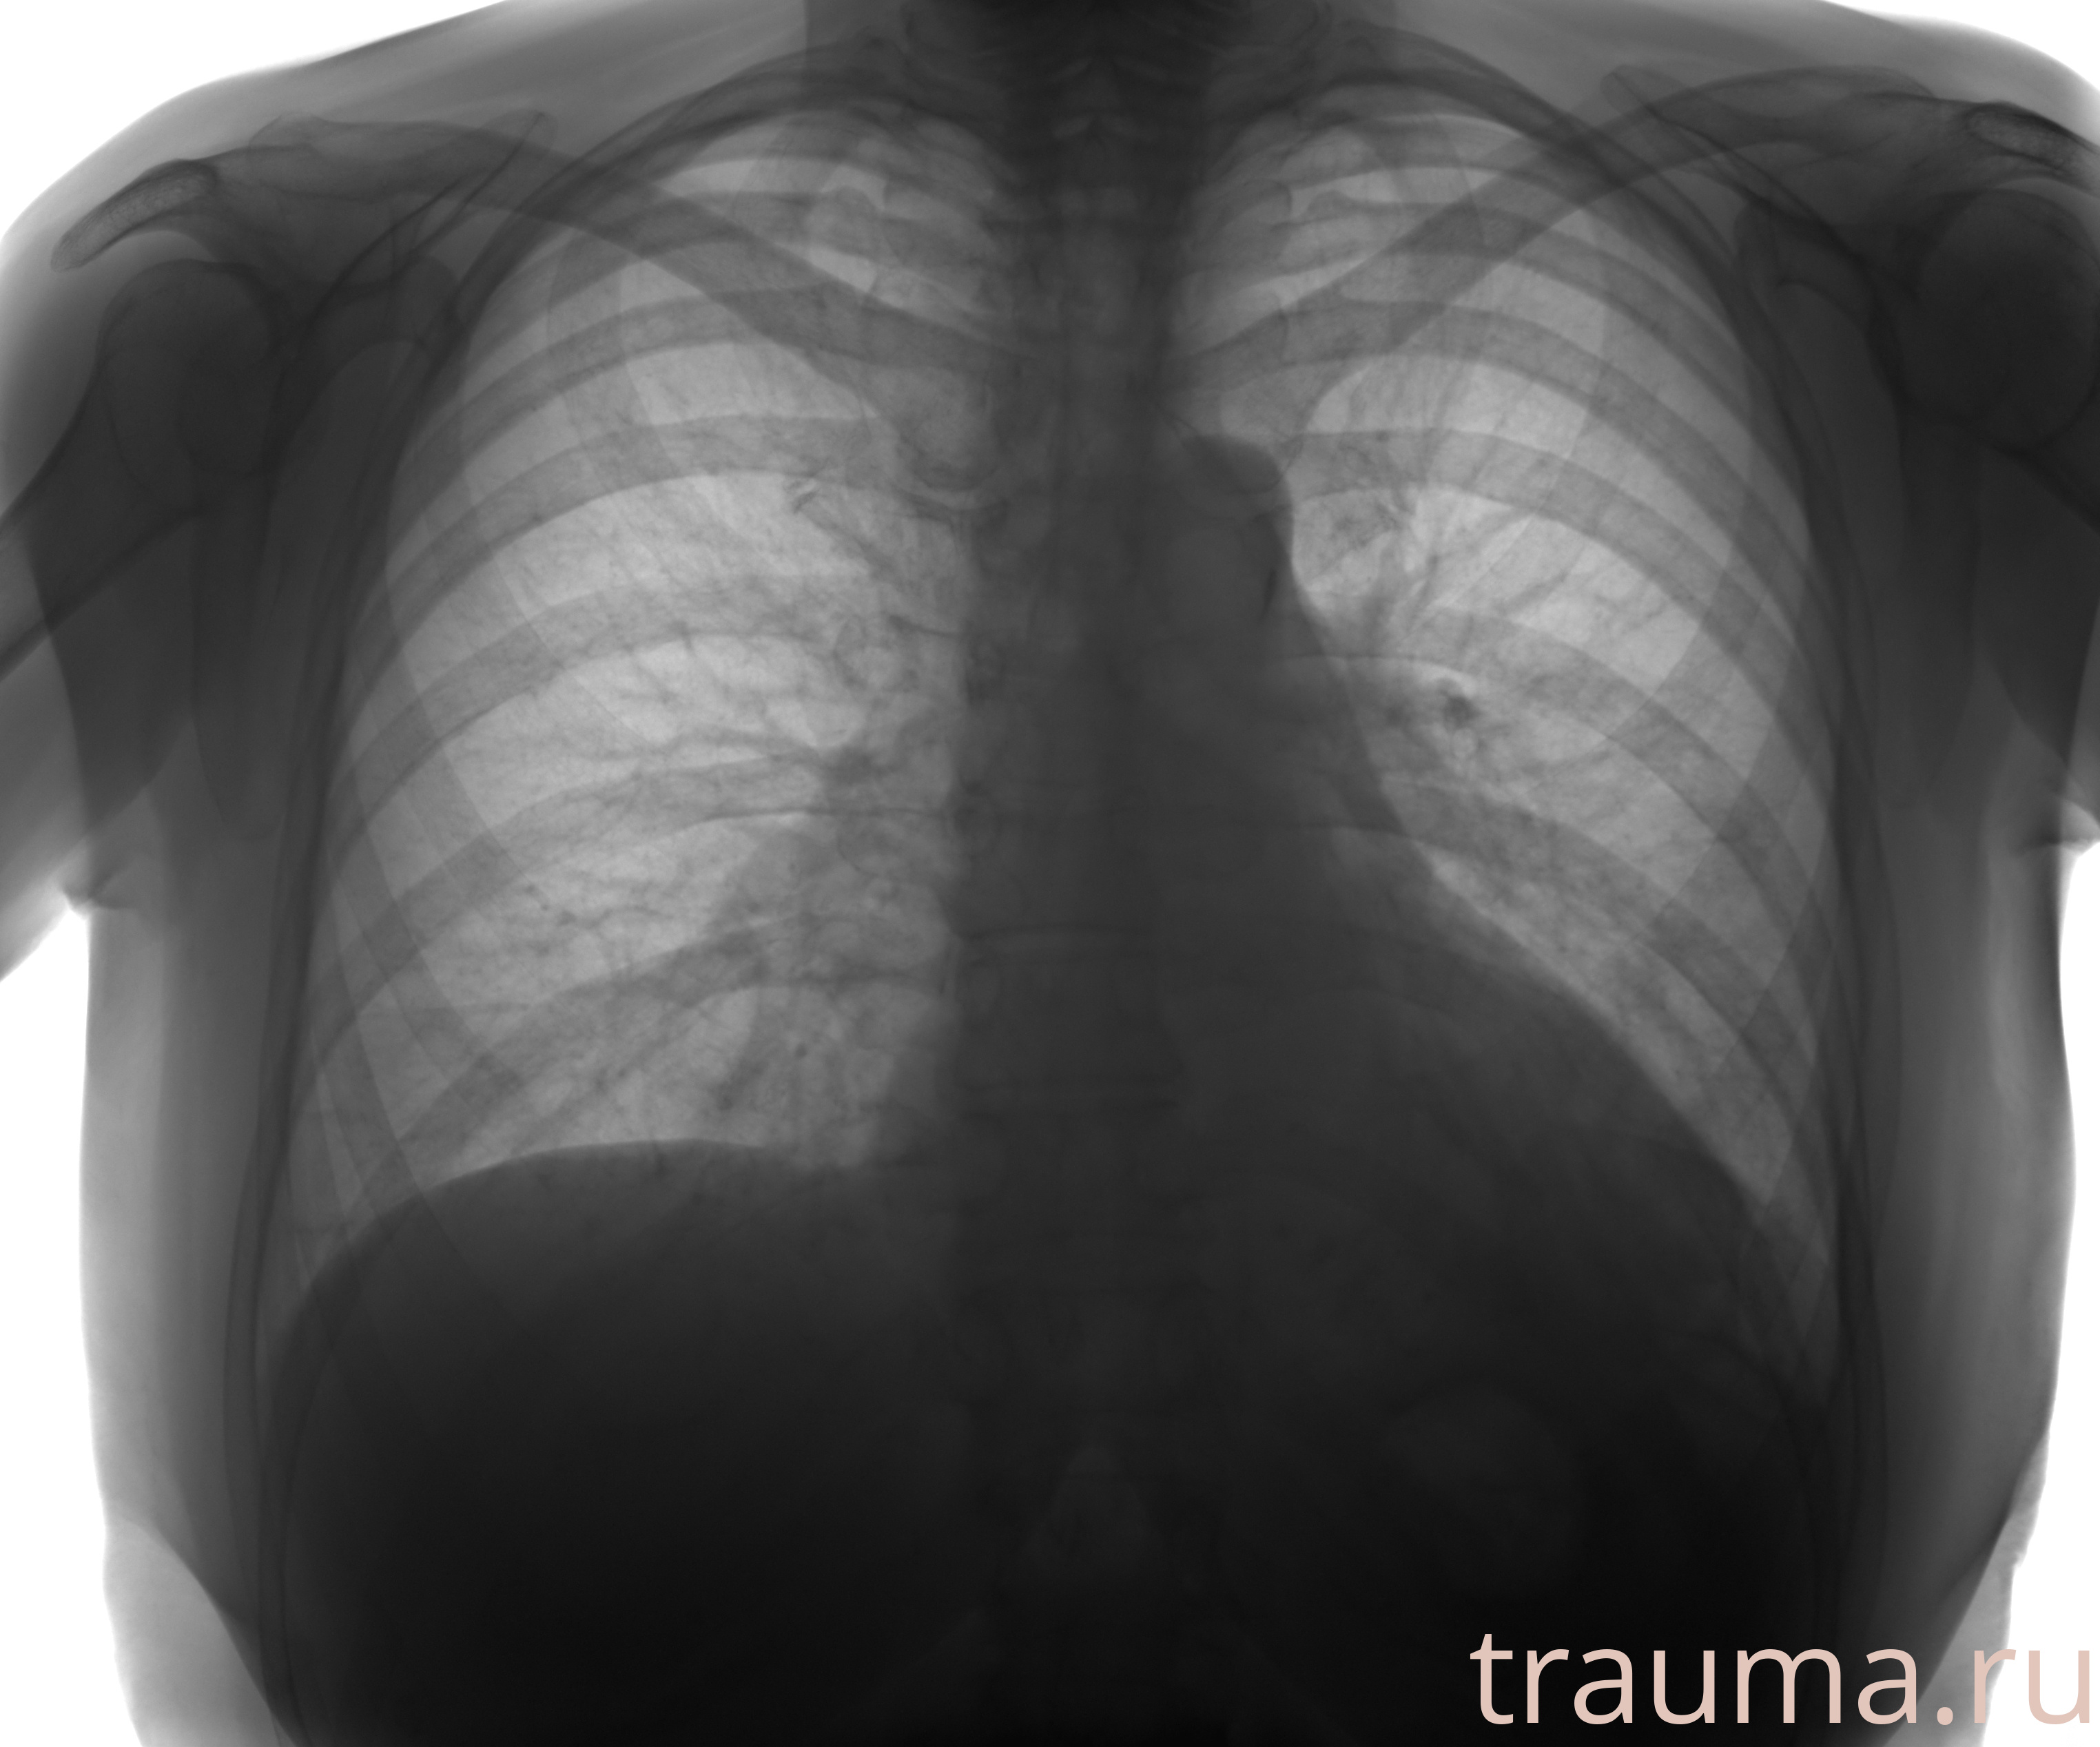

Рентгенограммы

Рентген на дому: по вашему адресу приезжает врач-рентгенолог, травматолог-ортопед с мобильным рентгеновским аппаратом, проводит диагностику травмы или заболевания, делает необходимые рентгенограммы, дает рекомендации по дальнейшему лечению. Получить качественные снимки в домашних условиях возможно благодаря уникальной методике, разработанной МосРентген Центром для института  Склифосовского

Яркость: 1   Контраст: 1   Инвертировать: 0 Увеличение: 1

Перетаскивайте мышь вверх/вниз для контраста, влево/право для яркости. Прокрутка колесом изменяет масштаб. Нажмите Сбросить для возврата к исходному изображению. При увеличении держите мышь в той области, которую хотите рассмотреть.